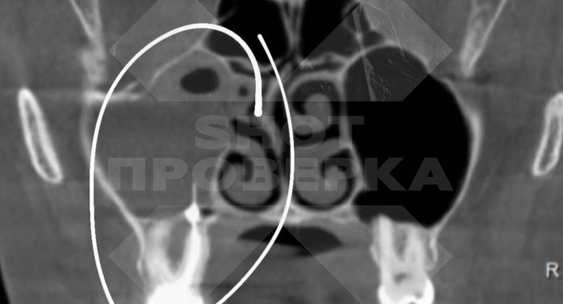

Судя по снимку, в носовой пазухе пациентки оказались инородные предметы.Общественная служба новостей

Выяснилось, что речь идет о трех пломбах и куске стоматологического инструмента.Общественная служба новостей